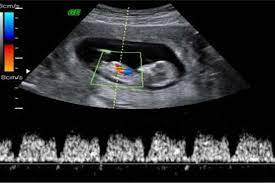

El perímetro craneal del bebé expresado en milímetros. Esta medida se toma entre las semanas 7 y 13 del embarazo es decir en la primera ecografía que se realiza para confirmar el embarazo. Ultrasonido de diagnóstico es una técnica de diagnóstico no invasiva que se utiliza para producir imágenes dentro del cuerpo.

Ultrasonido de diagnóstico es una técnica de diagnóstico no invasiva que se utiliza para producir imágenes dentro del cuerpo. Que significa cc en un ultrasonido. CRL Diámetro Biparietal Longitud del Fémur Circunferencia Abdominal Edad Gestacional etc. El perímetro abdominal del bebé expresado en milímetros. Aproximadamente la longitud del feto es 7 veces mayor que la del fémur. EPF en español estimación del peso del feto en gramos. Es la fecha estimada del parto.